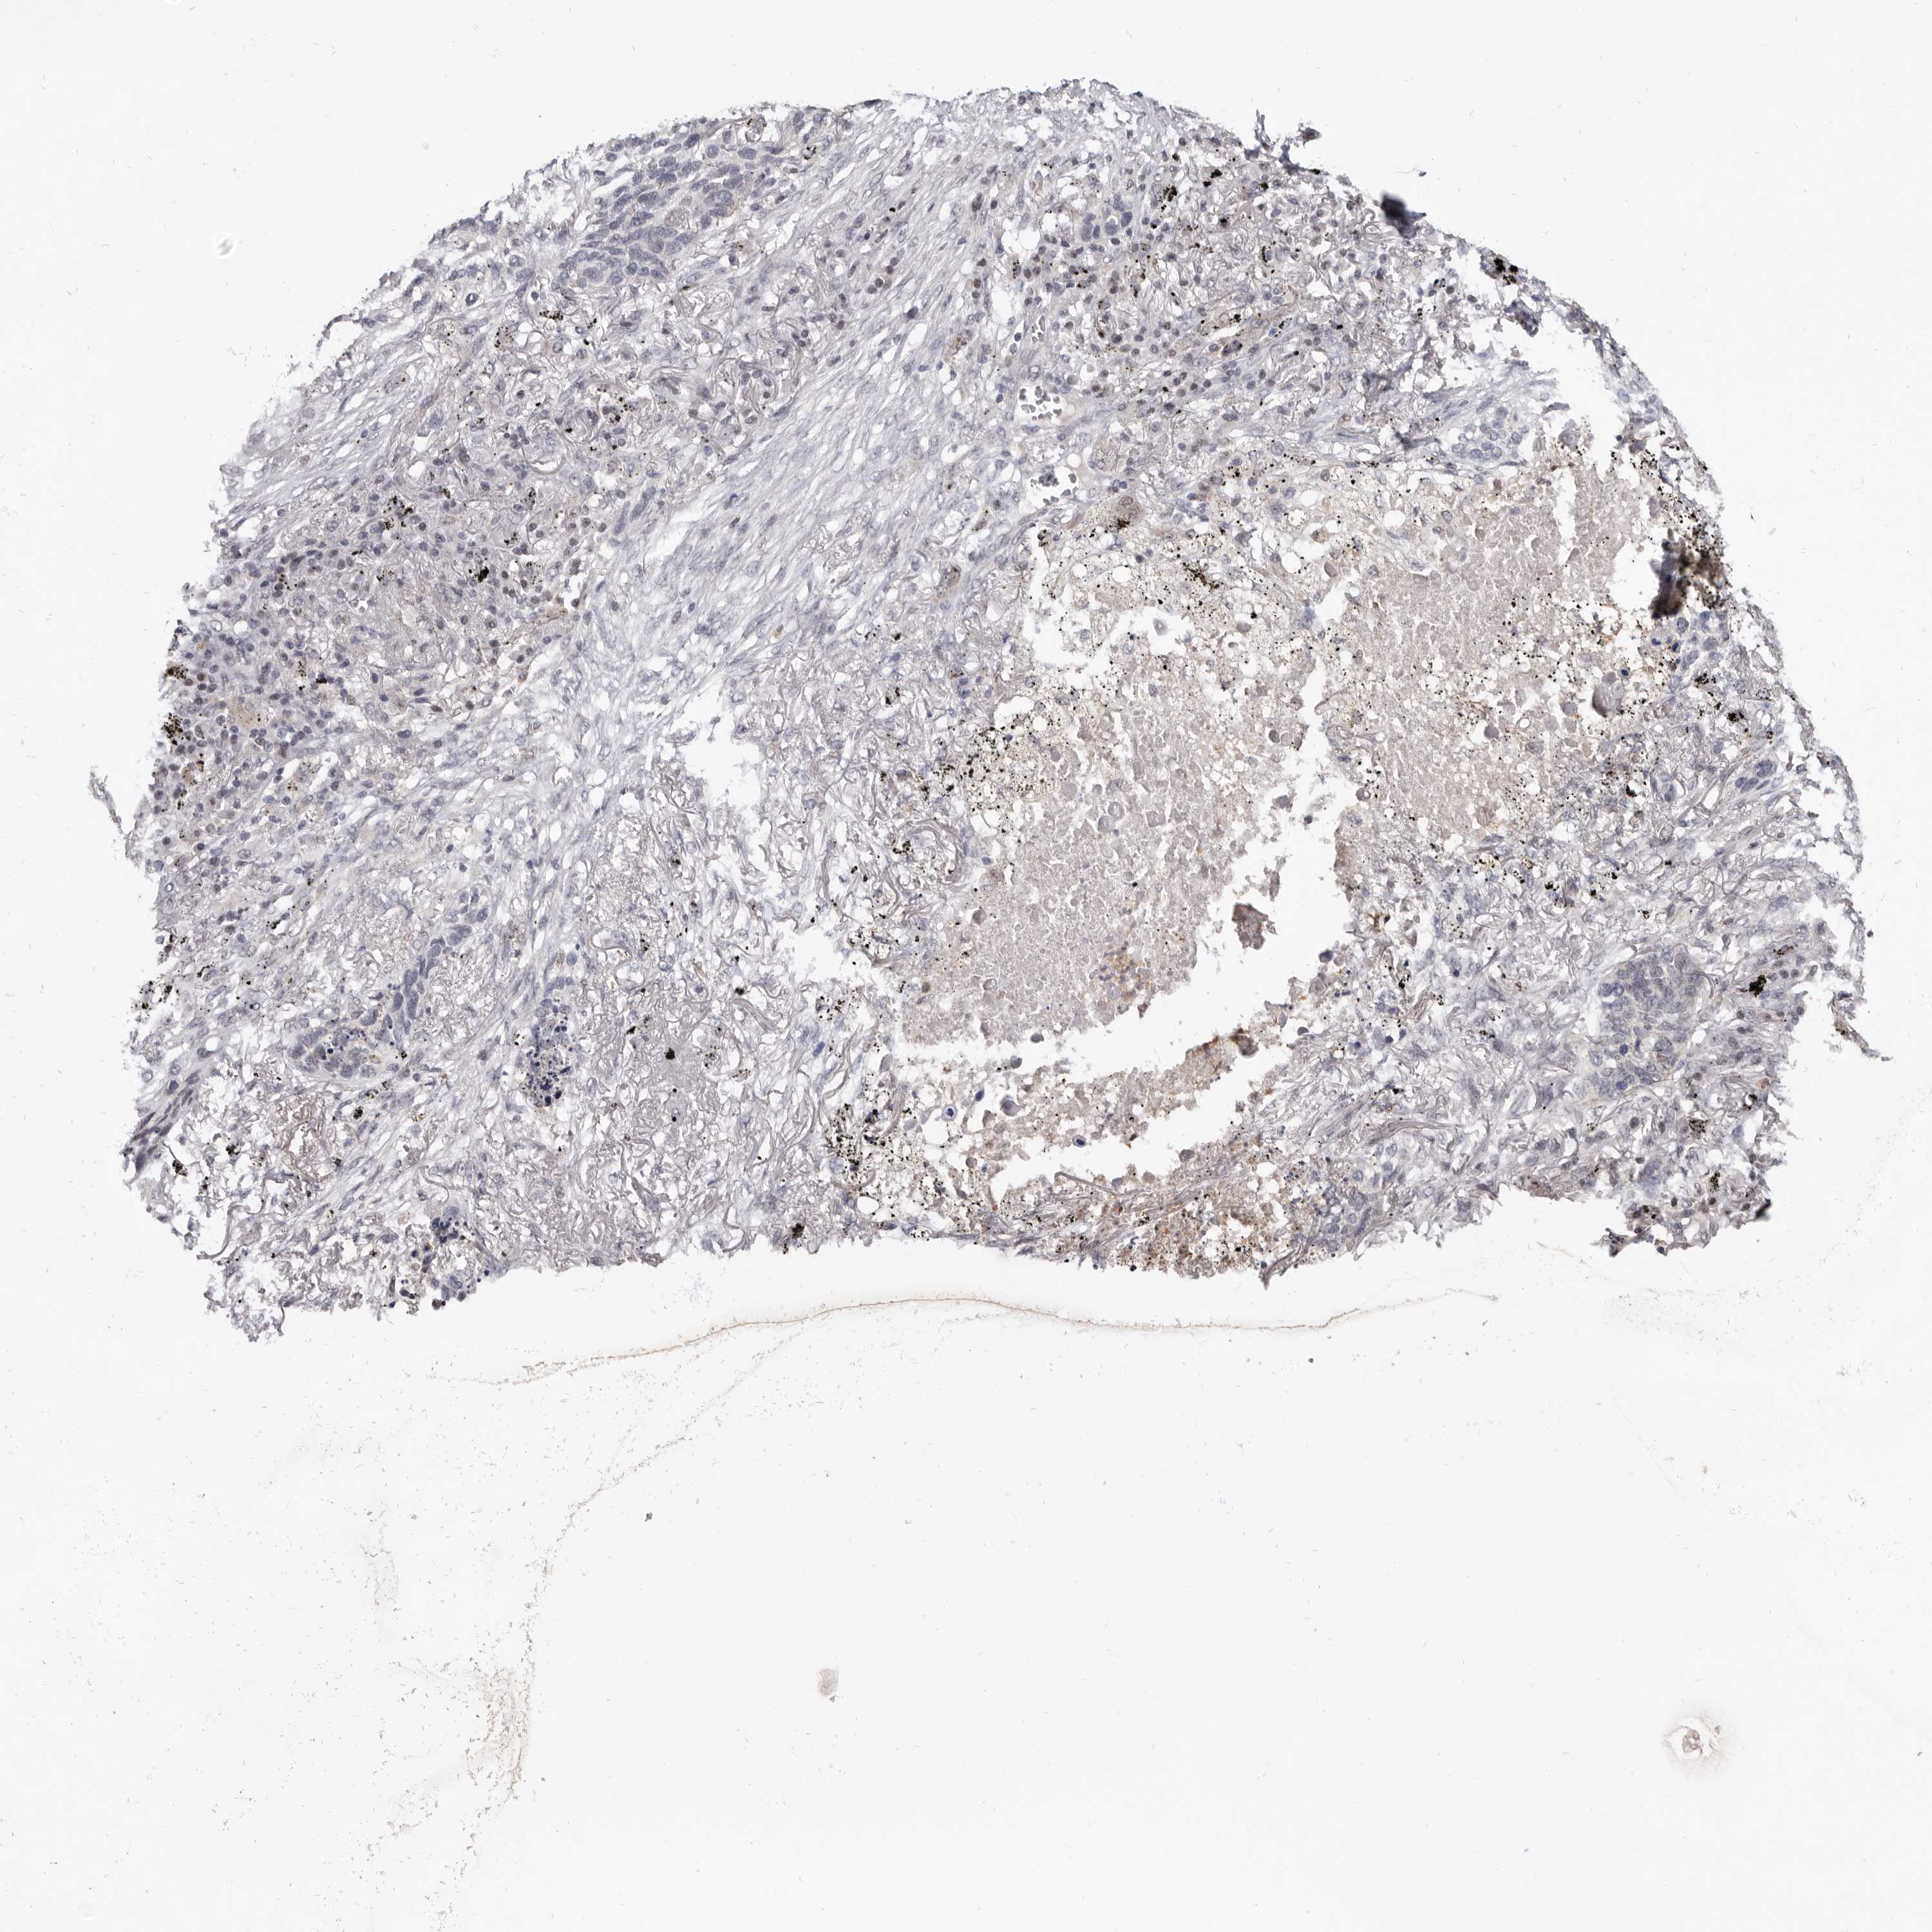

LUNG SQUAMOUS CELL CARCINOMA (TCGA) - Interactive survival scatter ploti

The Survival Scatter plot shows the clinical status (i.e. dead or alive) for all individuals in the patient cohort, based on the same data that underlies the corresponding Kaplan-Meier plots. Patients that are alive at last time for follow-up are shown in blue and patients who have died during the study are shown in red.

The x-axis shows the expression levels (FPKM) of the investigated gene in the tumor tissue at the time of diagnosis. The y-axis shows the follow-up time after diagnosis (years). Both axes are complimented with kernel density curves demonstrating the data density over the axes. The top density plot shows the expression levels (FPKM) distribution among dead (red) and alive patients (blue). The right density plot shows the data density of the survived years of dead patients with high and low expression levels respectively, stratified using the cutoff indicated by the vertical dashed line through the Survival Scatter plot. This cutoff is automatically defined based on the FPKM cutoff that minimizes the p-score. The cutoff can be changed by dragging the vertical line or by entering a cutoff value in the square labeled "Current cut-off".

Under the Survival Scatter plot the p-score landscape (black curve; left axis) is shown together with dead median separation (red curve; right axis). Dead median separation is the difference in median mRNA expression between patients who have died with high and low expression, respectively. It is calculated as follows: median FPKM expression of dead patients with high expression - median FPKM expression of dead patients with low expression. This is intended to aid the user in visually exploring custom cutoffs and the associated p-scores and dead median separation.

Individual patient data is displayed and can be filtered by clicking on one or more of the category buttons on the top of the page. Categories describing expression level and patient information include: high, low, alive, dead, female, male and tumor stages. The scale of the x-axis can be toggled between linear and log-scale by clicking on the "x log" button. Mouse-over function shows TCGA ID, patient information and mRNA expression (FPKM) for each patient.

& Survival analysisi

Kaplan-Meier plots summarize results from analysis of correlation between mRNA expression level and patient survival. Patients were divided based on level of expression into one of the two groups "low" (under cut off) or "high" (over cut off). X-axis shows time for survival (years) and y-axis shows the probability of survival, where 1.0 corresponds to 100 percent.

CGN is not prognostic in Lung Squamous Cell Carcinoma (TCGA)

Best expression cut offi

Based on the FPKM value of each gene, patients were classified into two groups and association between prognosis (survival) and gene expression (FPKM) was examined. The best expression cut-off refers the FPKM value that yields maximal difference with regard to survival between the two groups at the lowest log-rank P-value. Best expression cut-off was selected based on survival analysis .

When clicking on this number, the vertical dashed line indicating cut-off, the interactive survival plot, and the Kaplan-Meier curve will be adjusted to show results based on the best expression cut-off.

: 13.71

P scorei

Log-rank P value for Kaplan-Meier plot showing results from analysis of correlation between mRNA expression level and patient survival.

N/A

5-year survival highi

5-year survival for patients with higher expression than the expression cutoff.

For melanoma and glioma, 3-year survival is shown.

5-year survival lowi

5-year survival for patients with lower expression than the expression cutoff.

TCGA RNA samplesi

RNA-seq data is reported as average FPKM (number Fragments Per Kilobase of exon per Million reads), generated by the The Cancer Genome Atlas (TCGA) .

Normal distribution across the dataset is visualized with box plots, shown as median and 25th and 75th percentiles. Points are displayed as outliers if they are above or below 1.5 times the interquartile range. FPKM values of the individual samples are presented next to the box plot.

Average pTPM 9.6

Number of samples 489